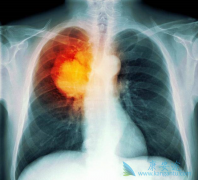

在目前已经公布的不同EGFR-TKI治疗晚期肺癌的III期临床研究中,药物性肝损伤(DILI)的发生率为5%-55.3%,≥3级的发生率为0.4%-26.3%。除阿法替尼外,多数 EGFR-TKI 主要通过肝脏酶系代谢。有研究认为EGFR-TKI的肝毒性与其活性代谢产物的代谢有关,而诱 ...

针对EGFR阳性晚期非小细胞肺癌(NSCLC)一线治疗,多个随机对照研究显示,EGFR-TKI 吉非替尼 、厄洛替尼和阿法替尼对比化疗可显著改善患者的无进展生存期,且三级以上不良反应显著低于化疗,奠定了吉非替尼、厄洛替尼和阿法替尼在EGFR突变晚期NSCLC一线 ...